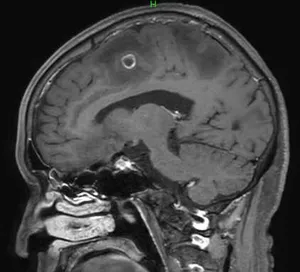

MR検査はがん診療において、CT検査と比較してより詳細な検査が可能です。

各臓器において浸潤範囲を描出することができ、治療範囲の決定のための広がり診断をすることができます。MRI検査は検査時間が長く、撮像できる範囲に制限があります。

MRI検査では造影剤が使用されます。

頭部造影MRI検査画像 頭部造影MRI検査画像 頭部造影MRI検査画像

頭部造影MRI検査画像(肺がん脳転移)